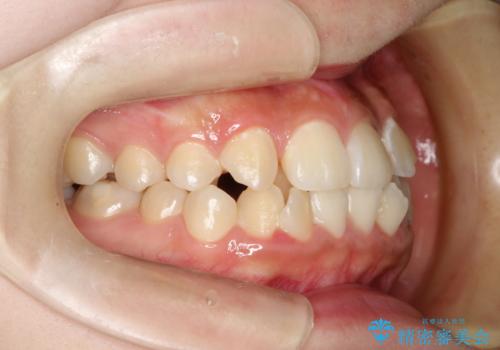

- 上下の前歯に激しい段差がある**重度の叢生(がたつき)**を主訴にご来院されました。精密検査の結果、歯をきれいに並べるためのスペースが圧倒的に不足していたため、上下左右の4番目の歯(第一小臼歯)を計4本抜歯する計画を立案しました。

本症例では、まず抜歯した大きなスペースを効率よく使い、歯の根元から大きく動かす必要があるため、初期段階にワイヤー矯正を採用。その後、細かな噛み合わせの調整や仕上げにインビザラインを使用する「ハイブリッドな矯正治療」で、期間の短縮と精度の高い仕上がりを目指しました。

ワイヤー矯正による先行治療: 最初のステージでは、ワイヤー装置を使用して抜歯したスペースへ歯を大きく移動させました。重度の叢生の場合、ワイヤーを用いることで歯のねじれや大きな移動をスピーディーに行うことができ、治療期間の短縮につながります。